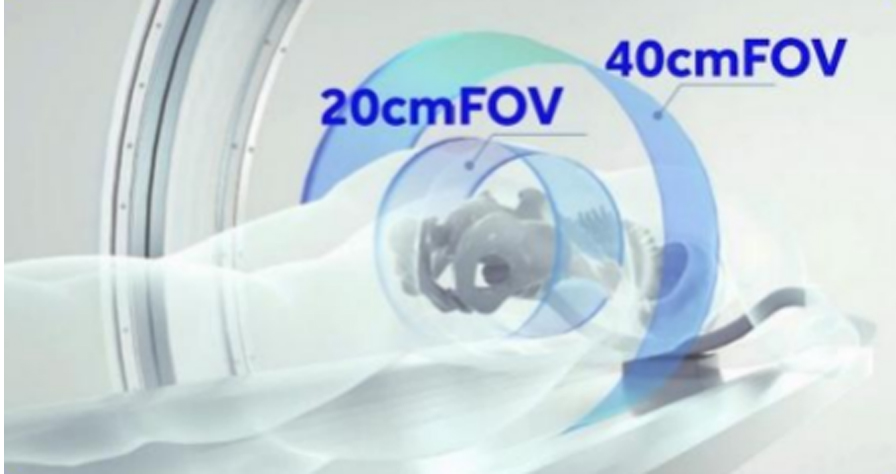

40cm 大視野掃描

采用更寬的平板探測器與影像重建技術,實現40cm 的三維掃描直徑,提高更寬闊的影像視野,適用于:

√ 重度脊柱側彎與后凸畸形 √ 骨盆骨折